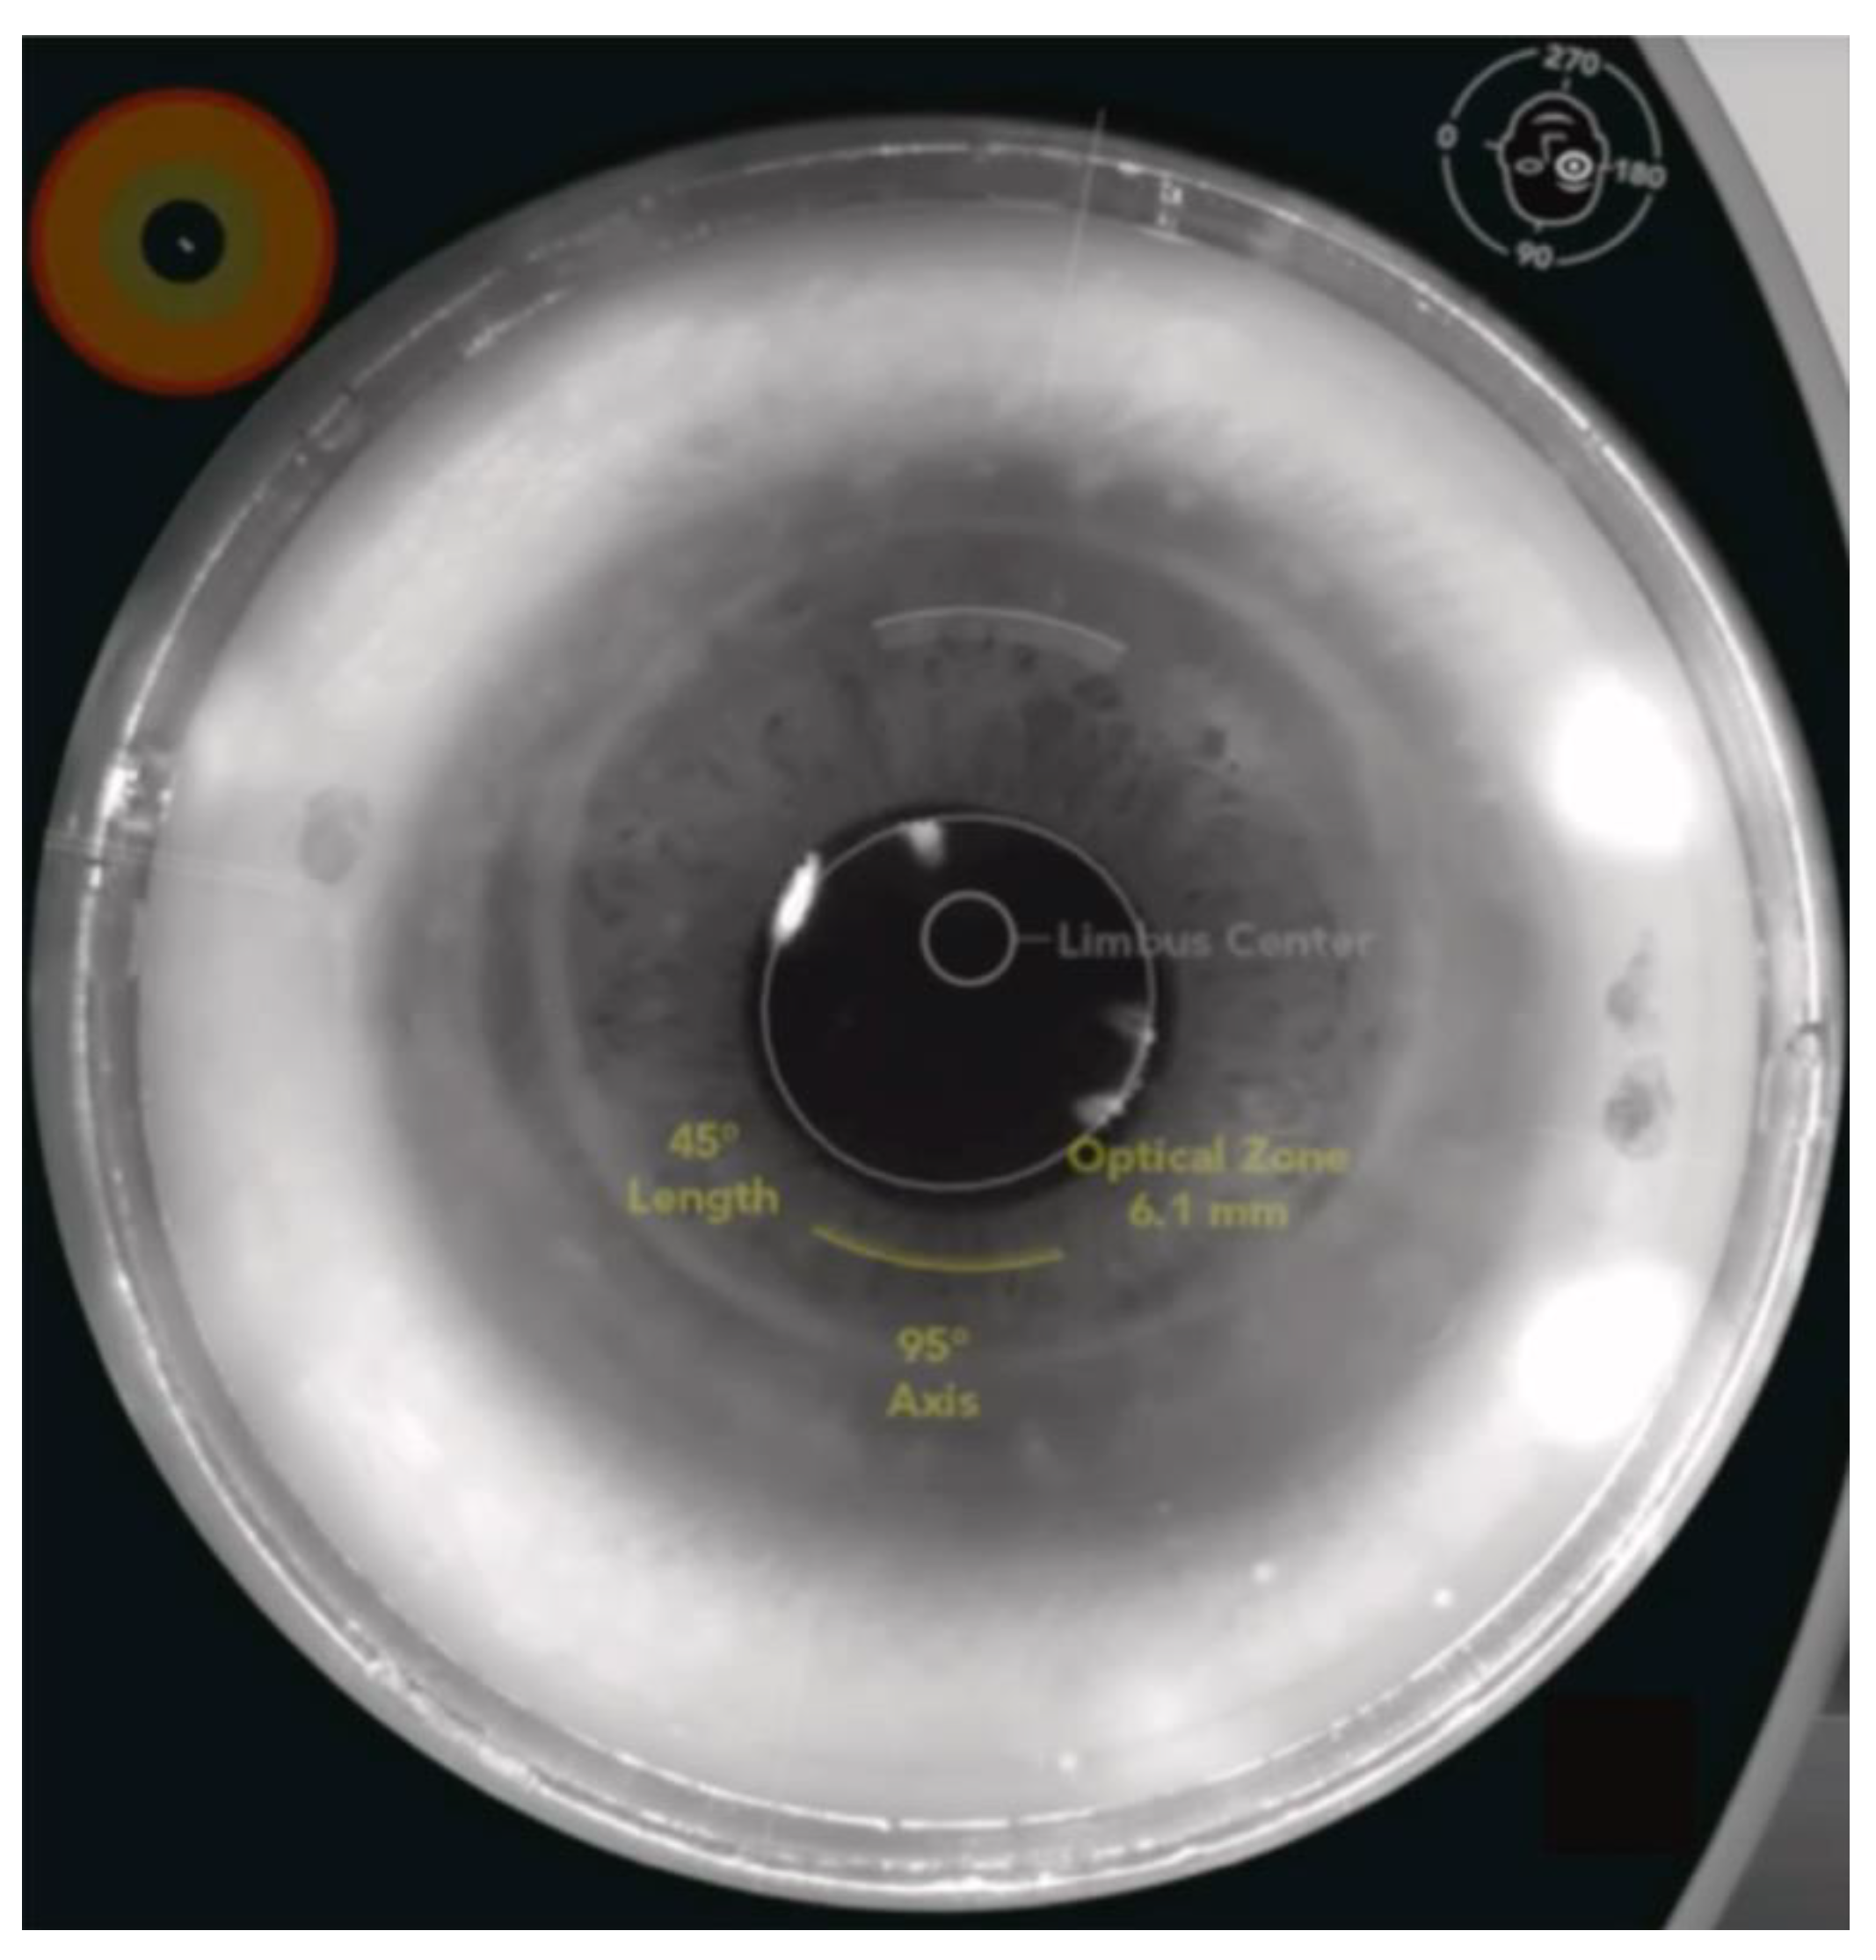

3.1.3. Femtosecond Laser-Assisted Astigmatic Keratotomy (FS-AK)

- Chang, J.S.M. Femtosecond laser-assisted astigmatic keratotomy: A review. Eye Vis. 2018, 5, 6. [Google Scholar] [CrossRef]

- Vickers, L.A.; Gupta, P.K. Femtosecond laser-assisted keratotomy. Curr. Opin. Ophthalmol. 2016, 27, 277–284. [Google Scholar] [CrossRef] [PubMed]

- Schwarzenbacher, L.; Schartmüller, D.; Roeggla, V.; Meyer, E.; Leydolt, C.; Menapace, R. One-Year Results of Arcuate Keratotomy in Patients with Low to Moderate Corneal Astigmatism Using a Low-Pulse-Energy Femtosecond Laser. Am. J. Ophthalmol. 2021, 224, 53–65. [Google Scholar] [CrossRef]